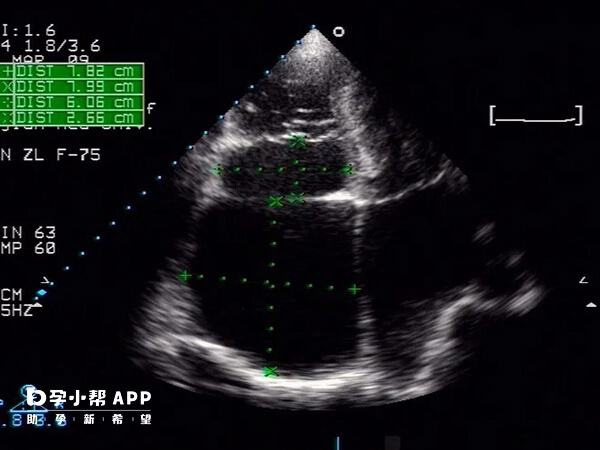

移植后需按时检测血hCG值,明确怀孕后遵医嘱进行B超检查,及时发现胚胎位置异常。